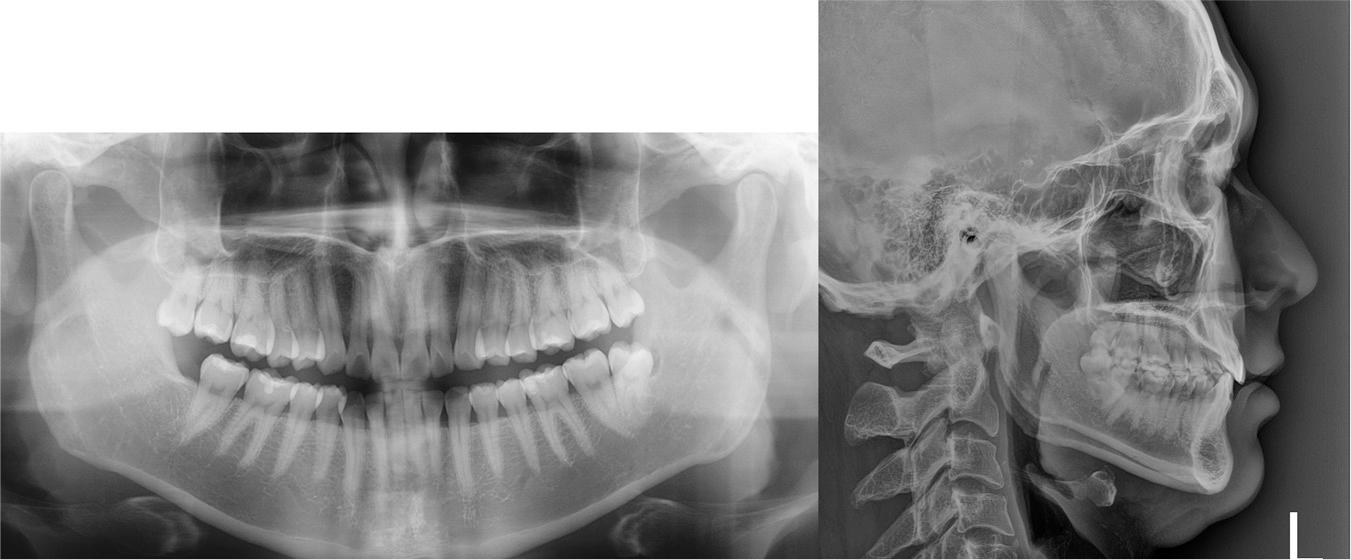

The panoramic radiograph showed a distally angulated left mandibular third molar, while the maxillary third molars had erupted in an upright position (Figure 2). The findings from the lateral cephalogram indicated a Class I skeletal pattern, with a slightly reduced mandibular plane angle (Figure 2, Table I). Additionally, the maxillary and mandibular incisors were retroclined.

Pre-treatment radiographic records, including panoramic and lateral cephalogram.